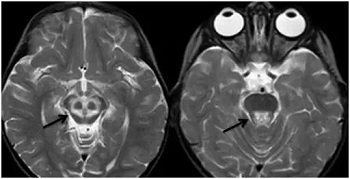

贾映海教授接着说,“小熊猫脸征”,中脑下部层面的双侧大脑脚、 上丘、 导水管、 导水管周围灰质核团、中央上核等构成了小熊猫脸的大体结构, 而双侧受累而呈长T2 信号的红核周围纤维束与短T2的中央被盖束勾勒出小熊猫的双眼。